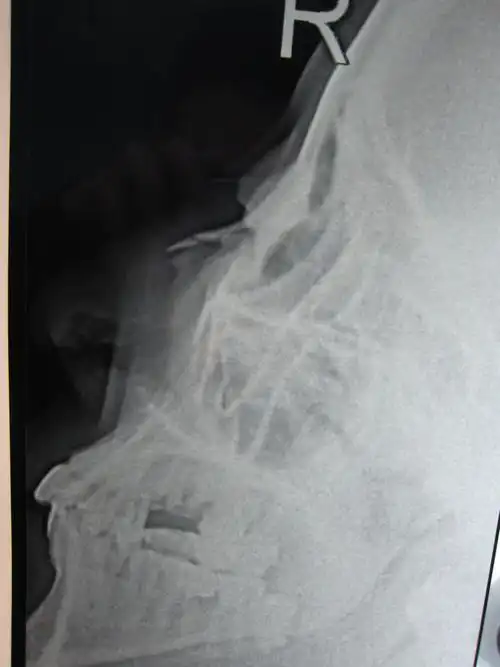

鼻骨骨折影像学诊断与鉴别

外伤致鼻骨骨折,颜面部皮肤软组织肿胀(附检查单,ct,x片).

请大家帮我看一下这个鼻骨是骨折吗?

外伤2天后做了鼻骨闭合复位,外伤6天后拍的x光片,x光片上有什么翁题